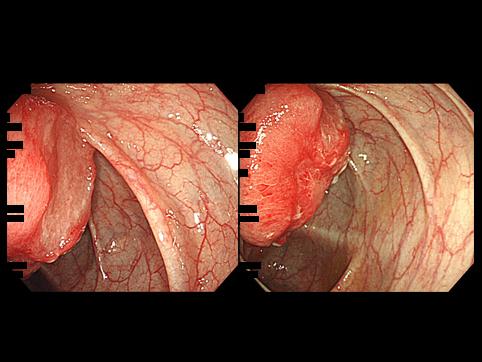

A case of malignant lymphoma in the ileum that was found due to the intussusception of the intestine.

[ Image ID:11078 ]

Malignant Lymphoma/Malignant lymphoma

Small intestine/Jejunum

Endoscopy

Type 1 Protuberant (polypoed) type/

35 - 40